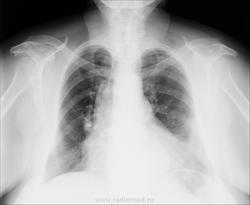

Грыжа ПОД? Дайте глоток бария. За 2 ребром справа что-то виднеется?

+1.Фиксированная грыжа пищеводного отверстия диафрагмы, с вероятностью~95%.

+ за грыжу, и за тень на фоне 2-го реба, только кажется это сосуды, на оригинале надо посмотреть. а одышка скорее всего из-за сердечных дел

А с легкими все в порядке? Нет ли картинки гиповентиляции верхней и средних сегментов лев. легкого. А ГПОД не периферический ли, м.б. с распадом и мт в парабронхеальные?

на прямом скорее кишка...

Это эхинококк, наверное.